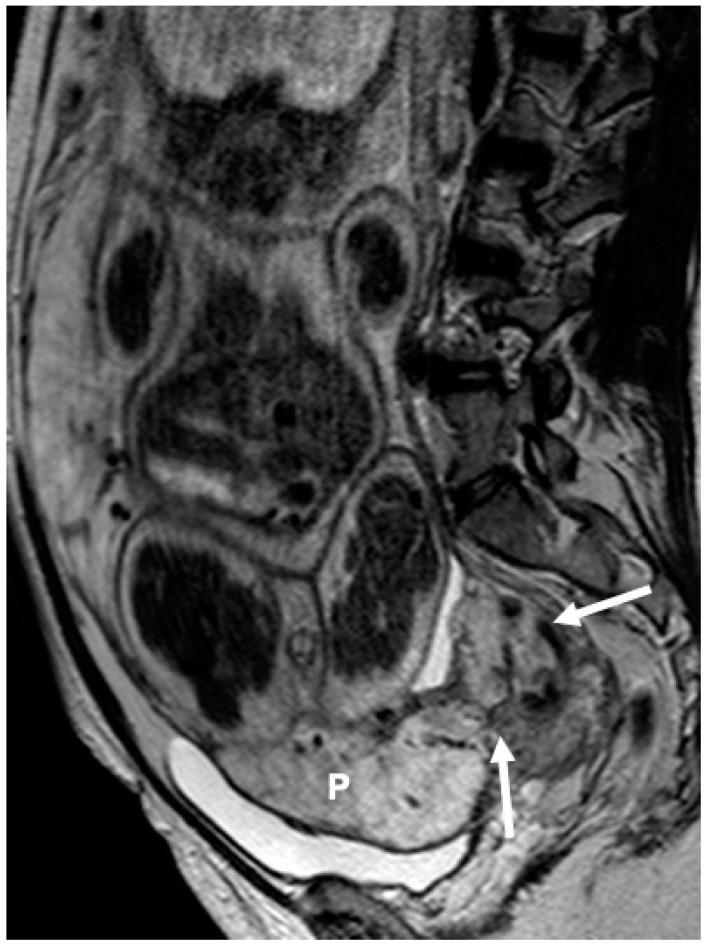

Placenta accreta spectrum (PAS) disorder is one of the leading causes of peripartum maternal morbidity and mortality; its early identification during pregnancy is of utmost importance to ensure the optimal clinical outcome. The aim of the present study is to investigate the possible association of the presence and type/location of placenta previa on MRI with PAS and maternal peripartum outcome. One hundred eighty-nine pregnant women (mean age: 35 years; mean gestational age: 32 weeks) at high risk for PAS underwent a dedicated placental MRI. All women underwent a C-section within 6 weeks from the MRI. All MRIs were evaluated by two experienced genitourinary radiologists for presence, type (complete/partial vs. marginal/low lying), and location (anterior vs. anterior-posterior vs. posterior) of placenta previa. Statistical analysis was performed for possible association of type/location of previa with placental invasiveness and peripartum outcomes. Intraoperative information was used as a reference standard. Complete/partial previa was detected in 143/189 (75.6%) and marginal/low lying previa in 33/189 (17.5%) women; in 88/189 (46.6%) women, the placenta had anterior-posterior, in 54/189 (28.6%) anterior and in 41/189 (21.7%) posterior. Complete/partial previa had an at least 3-fold probability of invasiveness and was more frequently associated with unfavorable peripartum events, including massive intraoperative blood loss or hysterectomy, compared to low-lying/marginal placenta. Posterior placental location was significantly associated with lower rates of PAS and better clinical outcomes. In conclusion, the type and location of placenta previa shown with MRI seems to be associated with severity of complications during delivery and should be carefully studied.

胎盘植入谱系障碍(PAS)是围产期孕产妇发病和死亡的主要原因之一;孕期早期识别对确保最佳临床结局至关重要。本研究旨在探讨MRI上前置胎盘的存在、类型/位置与PAS及孕产妇围产期结局之间的可能关联。189例PAS高危孕妇(平均年龄:35岁;平均孕周:32周)接受了专门的胎盘MRI检查。所有孕妇在MRI检查后6周内均接受了剖宫产。两名经验丰富的泌尿生殖放射科医生对所有MRI图像进行评估,以确定前置胎盘的存在、类型(完全性/部分性与边缘性/低置性)和位置(前位与前后位与后位)。对前置胎盘的类型/位置与胎盘侵入性及围产期结局之间的可能关联进行了统计分析。术中信息用作参考标准。143/189例(75.6%)孕妇检测到完全性/部分性前置胎盘,33/189例(17.5%)孕妇检测到边缘性/低置性前置胎盘;88/189例(46.6%)孕妇胎盘位于前后位,54/189例(28.6%)位于前位,41/189例(21.7%)位于后位。与低置性/边缘性胎盘相比,完全性/部分性前置胎盘的侵入可能性至少高3倍,且更常与不良围产期事件相关,包括术中大量失血或子宫切除术。胎盘后位与PAS发生率较低及更好的临床结局显著相关。总之,MRI显示的前置胎盘类型和位置似乎与分娩期间并发症的严重程度相关,应仔细研究。